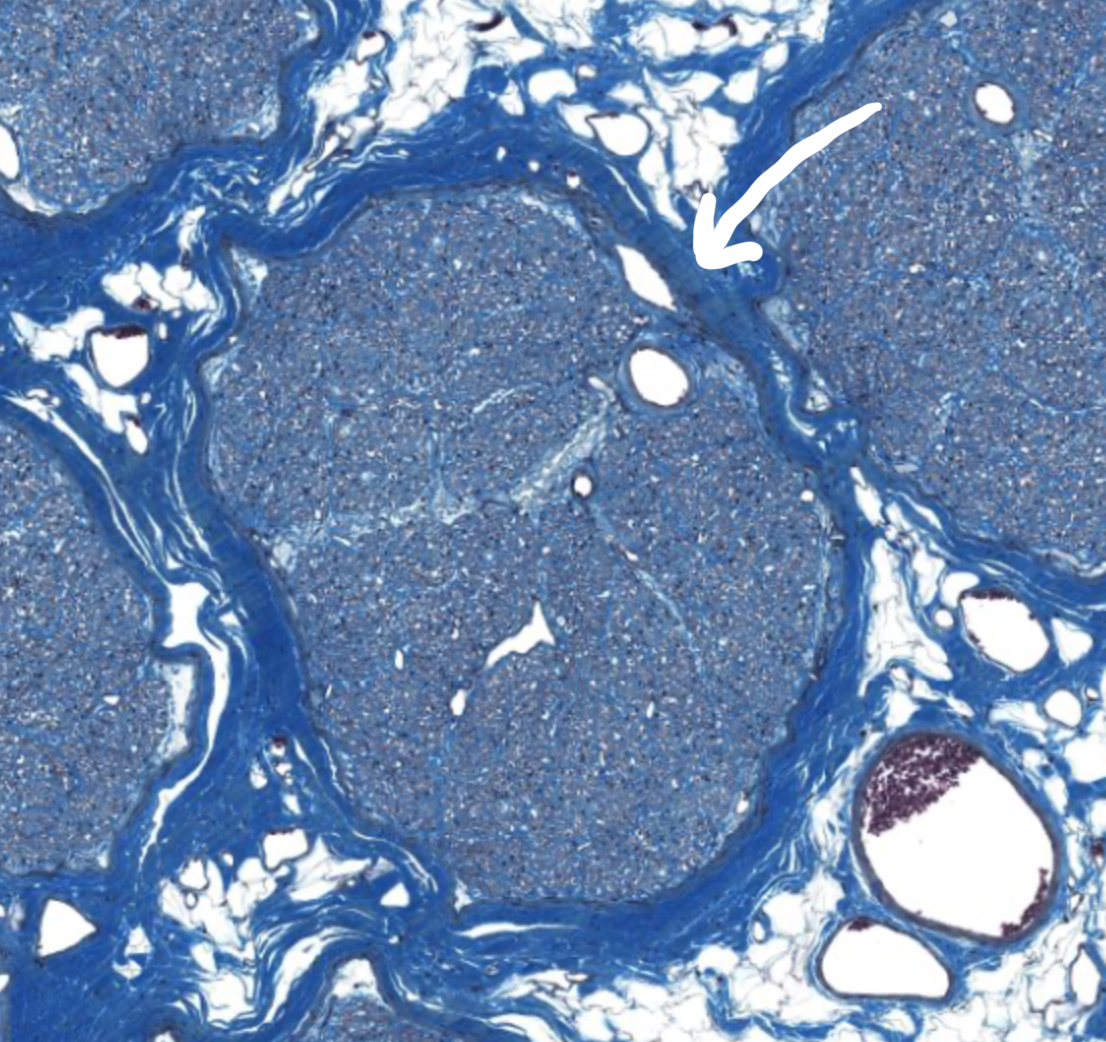

What is this structure

Epineurium of peripheral nerve

Perineurium of peripheral nerve

Endoneurium of peripheral nerve